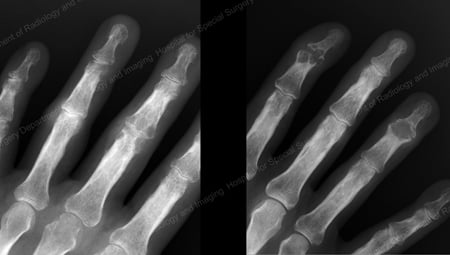

X-ray of gout of the distal finger joints

Figure 13: Gout of the Distal Finger Joints

X-ray of gouty destruction at multiple finger joints

Figure 15: Gouty Destruction at Multiple Finger Joints